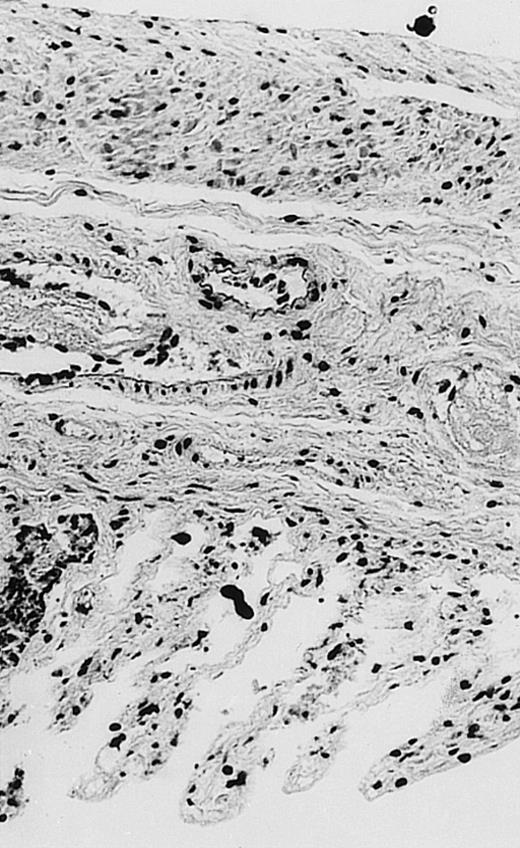

Pathologic findings in the small and large intestine were strikingly different depending on the treatment group. Figure 2A shows a representative pathologic sample from an animal assigned to the control group. Marked thinning of the bowel wall and extensive areas of epithelial cell sloughing was noted. Animals randomized to rhG-CSF treatment had minimal improvement in histologic findings with focal regions of preserved epithelium (Fig2B). Animals randomized to the rhIL-11 group showed substantial improvement with thickening of the epithelial layer and preservation of mucosal cell integrity (Fig 2C). Animals receiving both rhG-CSF and rhIL-11 had the most favorable histologic findings with normal mucosal thickness, minimal inflammatory changes, and preserved tissue architecture (Fig 2D). The composite analysis of the gastrointestinal pathology is provided in Table 1.

Histopathology of small intestinal mucosa cut in transection from an animal in each treatment group (study day 8). The upper panel (row 1) is a low power view (original magnification × 57); the lower panel (row 2) is a high power view (original magnification × 144). Note the diffuse thinning and necrosis of the mucosa with sloughing of intestinal epithelial cells in the control animal (A). There is progressive recovery of the thickness of the mucosa, reduction in inflammatory changes, and improved epithelial architecture with rhG-CSF (B), rhIL-11 (C), and combination therapy with rhG-CSF+IL-11 (D).